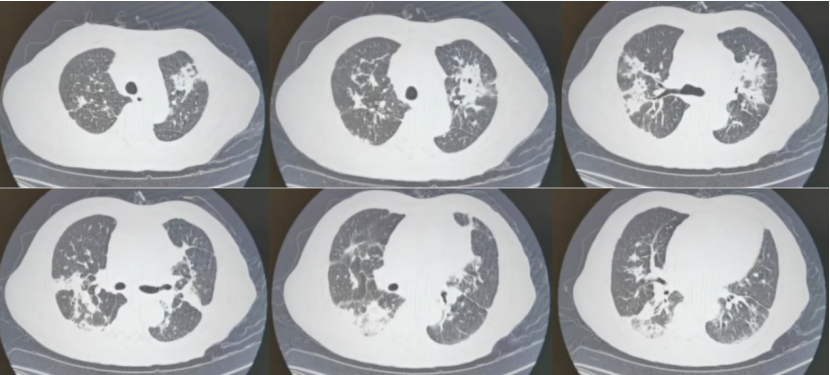

8月19日复查胸部CT可见双肺空洞样改变和下肺渗出性病变较前缓慢吸收(6)9月5日胸部CT发现肺部病变较前进一步吸收(7)9月12日(出院前)胸部CT可见病变吸收更明显(8)。患者除偶尔发热,整体情况较好。

6  复查胸部CT(2022-08-19)

7  复查胸部CT(2022-09-05)

8  复查胸部CT(2022-09-12)